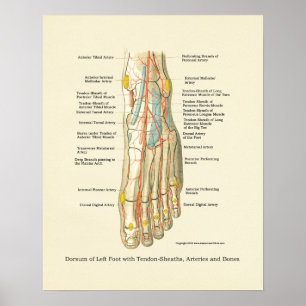

Poster interno da anatomia do pé & do tornozelo

Preço44,35 €